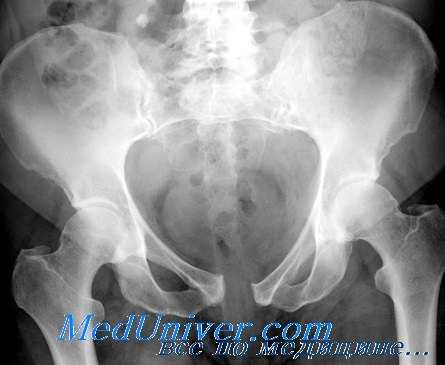

Рентгенография при подозрении перелома костей таза

При всех подозрениях на перелом таза рентгенологическое исследование следует начинать с оценки рентгенограмм таза в переднезадней проекции. Явные линии перелома обычно легко диагностируют. Кроме того, можно локализовать подозрительные на перелом поля и сделать соответствующие снимки в косых проекциях. Для точной диагностики подозреваемых переломов могут потребоваться боковые, аксиальные и переднезадние проекции с наклоном головного конца стола на 35°.